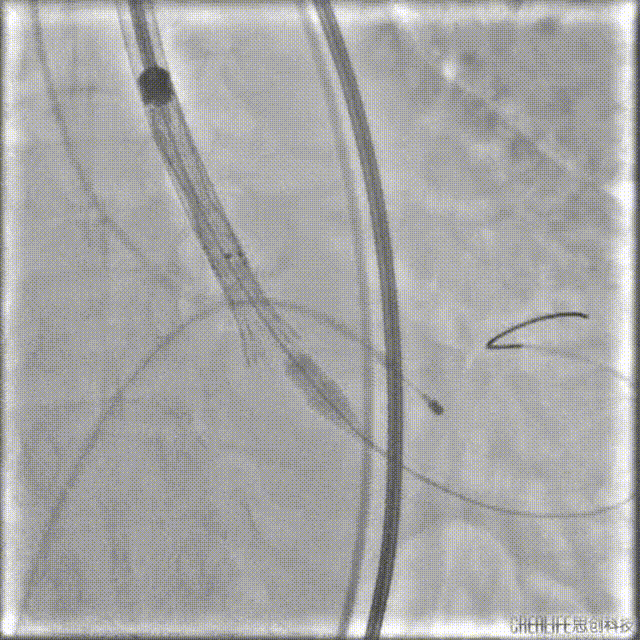

导丝跨瓣

选择22mm球囊进行预扩,结果显示具有明显腰征,无瓣周反流,遂即选择TaurusElite 26mm瓣膜,凭借其优异的柔顺性,轻松完成过弓。

球囊预扩

TaurusElite顺利过弓